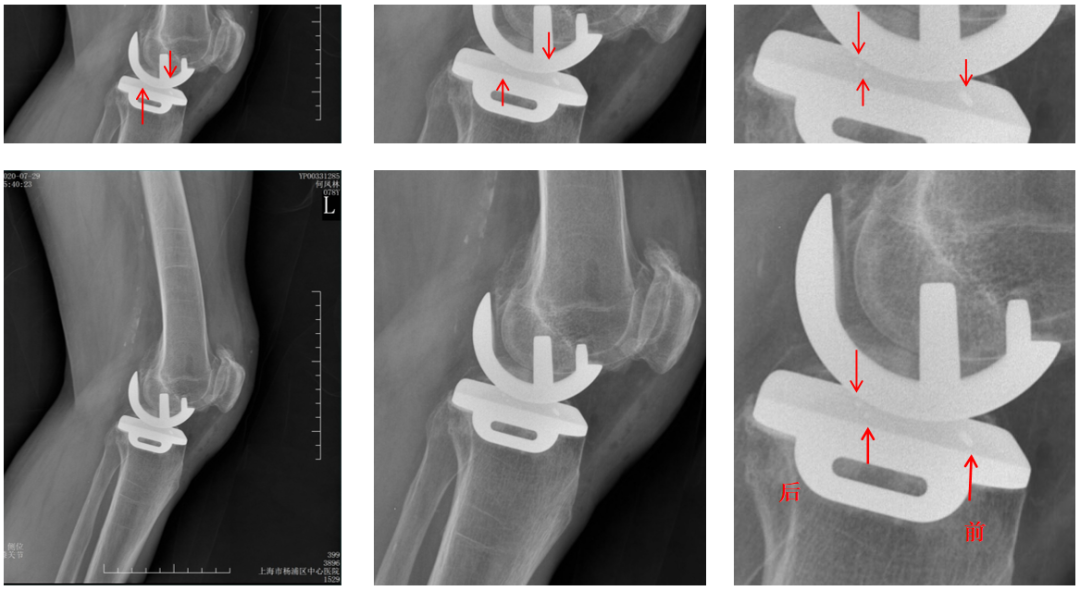

三、垫片(bearing)脱位

Bearing脱位多发生在UKA术后早期,发生率0.6%左右。

Bearing脱位主要原因包括:屈伸间隙不平衡,MCL损伤,以及假体位置不良,罕见bearing破裂。

Bearing脱位在正位片上显示股骨与胫骨假体关节面接触,侧位片显示bearing位于关节囊前方或者后方。

病例展示1

病例1:Bearing 前脱位

病例1:Bearing 前脱位的处理

病例展示2

病例2:Bearing 破裂( X-ray正位)

解读:两个点都在内侧

病例2:Bearing 破裂( X-ray侧位)

解读:股骨假体与胫骨假体间隙还存在,在图像放大4倍情况下,才依稀看到模糊的点.

病例2:Bearing 破裂

病例2:Bearing 破裂的处理